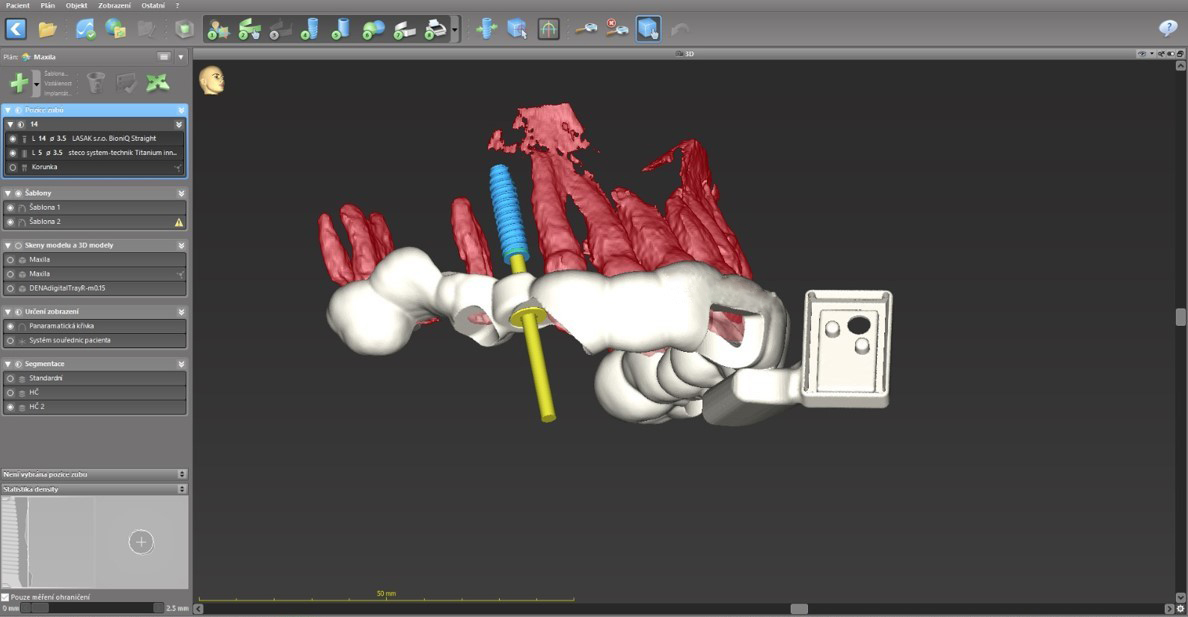

Um die Implantatsetzung so genau wie möglich zu gestalten (angesichts des begrenzten Knochenangebots sowie der Implantatlänge von 14 mm) und um die nahestehende Wurzel des Nachbarzahns zu umgehen, wurde eine kombinierte Operationsschablone entworfen.

Die auf Zähnen abgestützte Schablone enthielt eine Führungshülse für die statische schablonengeführte Pilotbohrung sowie einen Halter für den Sensor der dynamischen Navigation. Die Schablone wurde mittels 3D-Drucker hergestellt.

Die Präparation des Implantatbetts wurde mittels der Chirurgieschablone mit dem geführten Bohrer BioniQ® S2.9 unter Überwachung des Systems für die aktive Navigation DENACAM angefangen.

Die Schablone wurde entfernt und die Präparation wurde mit den konventionellen Instrumenten unter Verwendung des Systems für die aktive Navigation vollendet. Die genaue Einhaltung der geplanten Implantatposition wurde auf dem Bildschirm kontrolliert.